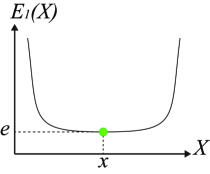

Uncertainty in object boundaries may arise from numerous sources, including graded composition (Udupa and Grevera, 2005), image acquisition artifacts, partial volume effects. Therefore, various image segmentation methods have been intentionally designed to output probabilistic or fuzzy results to better capture uncertainty in segmentation solutions (Grady, 2006; Zhang et al., 2001). Figure 6 demonstrates an example of how uncertainty information can be observed in an energy function. and in Figure 6 are two 1-D energy functions with the same optimal solution. However, segmentations near the minimal solution in have very similar energy values (high uncertainty) as opposed to solutions near the same optimal point in (less uncertainty/more certain). In fact, under the energy , a small perturbation in the image (e.g. additional noise) may change the segmentation result significantly. Given a probability distribution function over the label space, i.e. in (4), one way to calculate the uncertainty at pixel is to use Shannon’s entropy as: . The entropy can be used as an energy term in a segmentation energy function. In this case, lower entropy corresponds to larger certainty and vice versa.